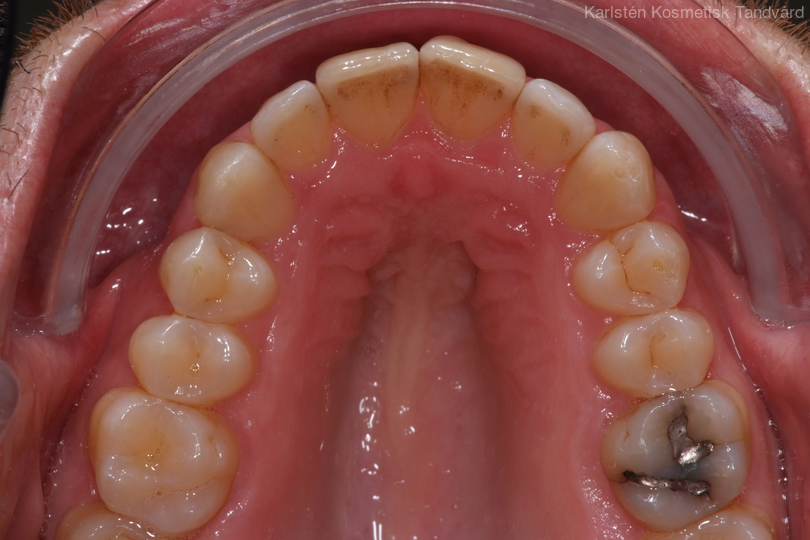

Tandreglering 3

35-årig man med smal och trångställd tandbåge. Vill ha ett jämnt leende. Behandling bestod av knappt 9 månader med genomskinliga Invisalignskenor.